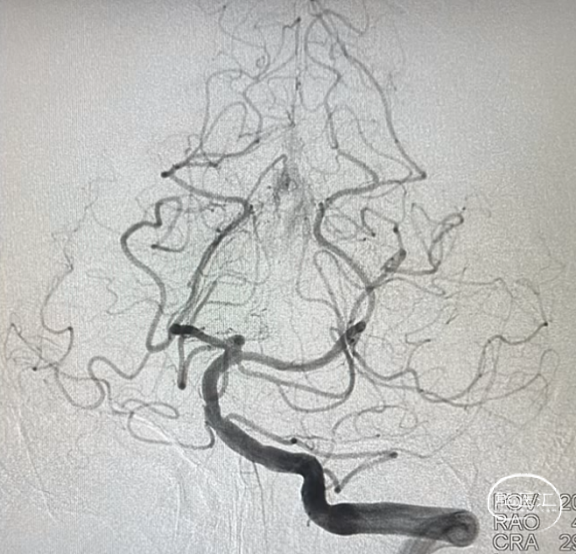

举个例子,大脑大静脉区硬脑膜动静脉瘘,这是左颈外动脉正位造影,可见大脑大静脉、直窦以及右侧横乙窦的提前显影